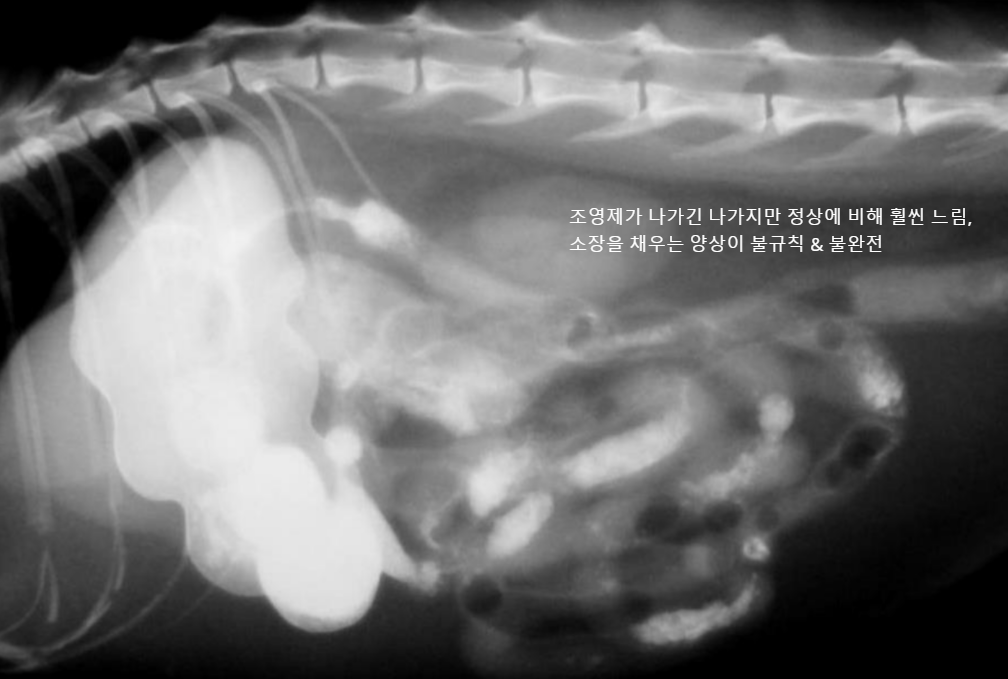

์กฐ์์ ๋ ๊ฐ์์ 1์๊ฐ 20๋ถ~2์๊ฐ, ๊ณ ์์ด์์ 1์๊ฐ ๋ด๋ก ๋ค ๋ฐฐ์ถ๋จ.

- ์ด๋ณด๋ค ์ค๋ ๊ฑธ๋ฆฌ๋ฉด ์์ ๋ฐฐ์ถ์ ๋ฌธ์ ๊ฐ ์๋ ๊ฒ. (๋ฐฐ์ถํ๋ ํ์ด ์ฝํด์ง, ํต๋ก๊ฐ ๋งํ, ์กฐ์์ ํก์ฐฉ/ํก์ ์ด๋ฌผ ์กด์ฌ)

| hairball, ์ฒ, ์ค (๊ณ ์์ด) - ์กฐ์์ ๋ฐฐ์ถ์ด ๋งค์ฐ ๋๋ฆผ (1์๊ฐ์ด๋ฉด ๋๊ฐ์ผ ํ๋๋ฐ, ๋ง 8์๊ฐ..) โ์ ๋จน๊ณ ์ ๋ ธ๋๋ฐ ๊ฐํ์ ์ผ๋ก ๊ตฌํ ํ๋ค โ โ ํค์ด๋ณผ ์์ฌ |

![]() |